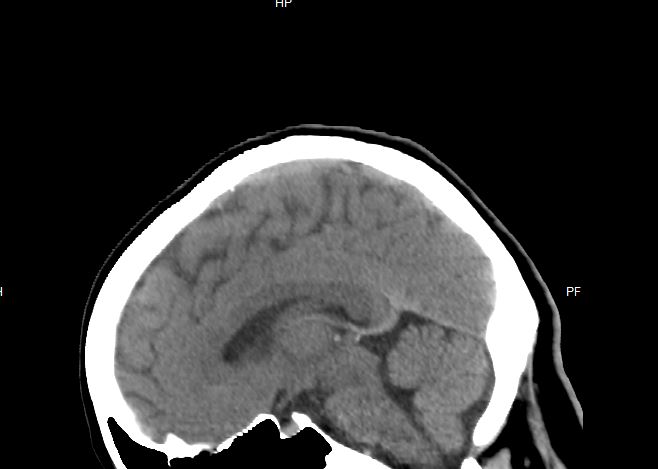

On a side note, it is fascinating seeing my own brain. When I first popped the CD into my laptop it took me a while to figure out how the program worked. When I did, I couldn't stop playing with the layers. Here are just a few screenshots. I never realized how lumpy my head is under the massive amount of hair on my head.